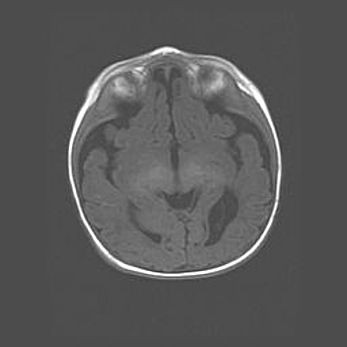

Сообщающаяся гидроцефалия. Кистозная энцефаломаляция головного мозга.

Возраст: 3 месяца 4 дня

Вес: 3100 г

Пол: женский

Окружность головы: 34 см

Срок гестации: 31 неделя

Кистозная энцефаломаляция головного мозга - одна из форм поражения головного мозга в детском возрасте. Характеризуется возникновением множественных и распространённых кист в коре, белом веществе и подкорковых образованиях головного мозга у плодов, новорождённых и детей раннего возраста. Развитие кистозной энцефаломаляции связано с внутриутробной асфиксией и гипотонией, родовой травмой, тромбозом синусов, пороками развития сосудов, инфекциями, сепсисом и другими причинами. Наиболее значимые инфекционные агенты: вирусы простого герпеса, цитомегалии, краснухи, токсоплазмы, энтеробактерии, золотистый стафилококк и другие.